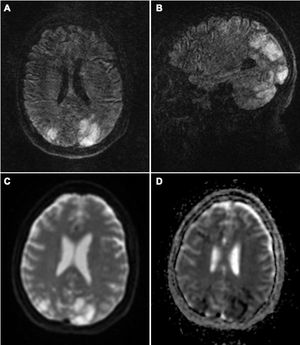

Brain MRI revealed T2-FLAIR hyperintensities in both cerebellar hemispheres, thalami, and parieto-occipital lobes, and border zones. Some lesions presented diffusion restriction (Fig. 1). Blood analysis showed glycaemia and ion levels within normal ranges, and no other significant alterations.

Brain MRI study: axial (A) and coronal (B) T2-FLAIR sequences showing hyperintense lesions in both cerebellar hemispheres and parieto-occipital lobes, predominantly on the left side, which do not correspond to the territory of a large vessel. DWI sequences (C) show diffusion restriction in some of these lesions, with low ADC values (D). All these signs are suggestive of severe PRES secondary to established infarction.